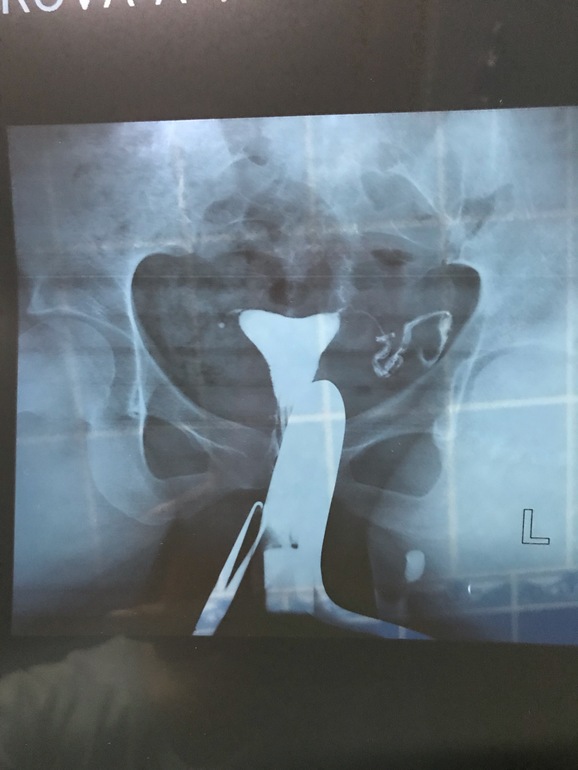

Гсг маточных труб. Пережила

ГСГ,ЭХО,МСГДевчонки посмотрите пожалуйста, может кто понимает в этом что то🤷🏼♀️Врач толком ничего не сказала

Жидкость вышла в брюшную полость но не так как хотелось бы( слова врача) что нужно лечение и что самой забеременеть без лечения никак🤷🏼♀️😞неужели все так плохо?(((((

Если что У МЕНЯ ТОЛЬКО ОДНА ТРУБА!

Труба извилистая, но проходима. А значит вполне можно Заб.

Кусочек этот смущает толи согнут толи перекручен